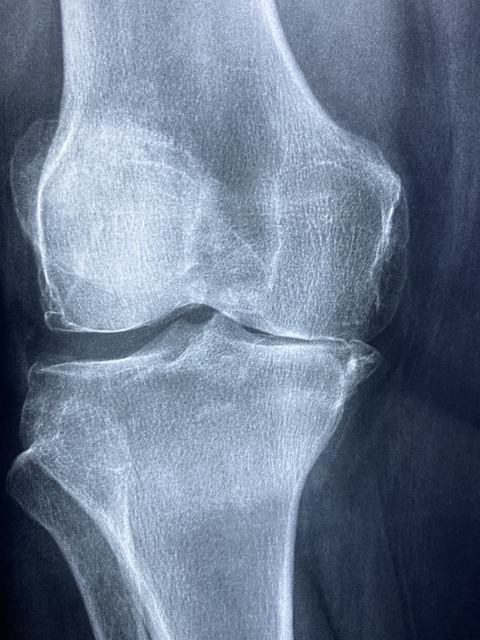

연골연화증의 진단 방법

연골연화증을 진단하기 위해서는 의사가 환자의 의료 기록을 검토하고 신체 검사를 실시하는 과정을 포함합니다.

- X-레이: 슬개골과 대퇴골 사이의 정렬 상태를 평가하고, 뼈의 구조적 문제가 있는지 확인합니다. 그러나 X-레이는 연골 자체는 보여주지 않습니다.

- 자기 공명 영상(MRI): MRI는 연골의 상태를 보다 상세하게 평가할 수 있으며, 연골연화증 진단에 특히 유용합니다. 연골의 손상 정도와 연화 상태를 정확히 보여줍니다.

- 관절경 검사: 드물게, 의사는 관절경을 사용하여 무릎 내부를 직접 검사할 수 있습니다. 이 방법은 연골의 손상을 직접 관찰하고 평가할 수 있어 정확한 진단을 제공합니다.